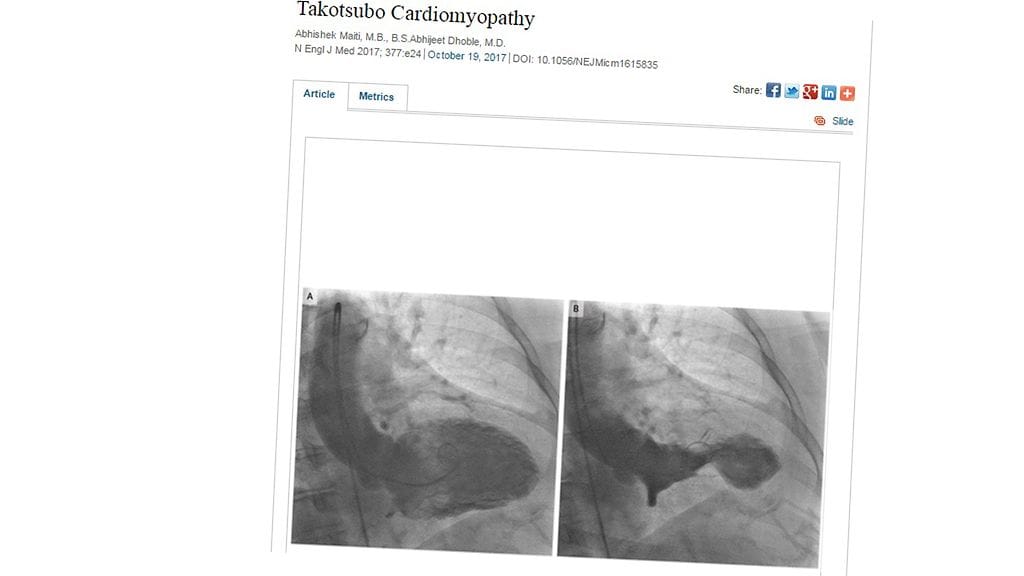

Lääkärit diagnosoivat 61-vuotiaalle naiselle sydäninfarktia muistuttavan takotsubo-kardiomyopatian, joka tunnetaan myös särkyneen sydämen oireyhtymänä. Tämä sydänhalvaus ilmenee tavallisesti jonkun järkyttävän tapahtuman, kuten läheisen ihmisen kuoleman jälkeen. Näin oli myös Simpsonin tapauksessa, joka oli vähän aikaa sitten menettänyt rakkaan lemmikkinsä, Yorkshirenterrieri Mehan.

Nainen oli ottanut koiran kuoleman niin raskaasti, että hänen sydämensä oli kirjaimellisesti särkynyt. Simpsonin tapaus esiteltiin tässä kuussa New England Journal of Medicine -julkaisussa, jossa oireyhtymän todetaan olevan todennäköisempi menopaussin ohittaneilla naisilla.